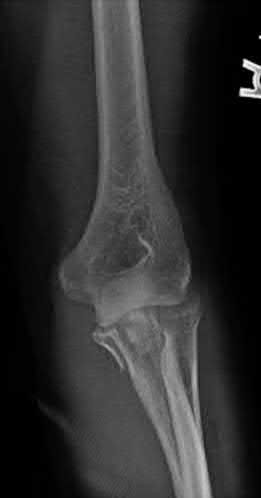

Question 20:

A 3-year-old girl is evaluated for severe, progressive bilateral genu varum. Radiographs demonstrate medial metaphyseal beaking, fragmentation, and depression of the proximal medial tibial physis. According to the Langenskiöld classification of infantile Blount's disease, at which stage does an overt physeal bony bar (epiphyseal-metaphyseal bridge) definitively form across the medial physis, conferring a high risk of recurrence without bar excision?

Options:

- Stage II

- Stage III

- Stage IV

- Stage V

- Stage VI

Correct Answer: Stage VI

Explanation:

The Langenskiöld classification describes progressive radiographic changes in infantile Blount disease. Stage I-IV show worsening metaphyseal beaking and stepping. Stage V shows a deep cleft separating the medial epiphysis into two portions. Stage VI is definitively characterized by the formation of a solid medial physeal bridge (bony bar) between the epiphysis and metaphysis, halting medial growth completely and often requiring bar resection along with osteotomy.